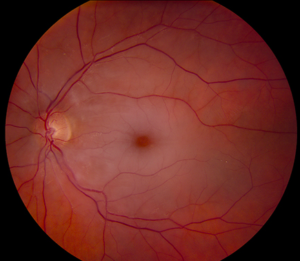

Wet ARMD;In wet age-related macular degeneration, abnormal blood vessels under the retina begin to grow toward the macula. Because these new blood vessels are abnormal, they tend to break, bleed, and leak fluid, damaging the macula and causing it to lift up and pull away from its base. This can result in a rapid and severe loss of central vision.

wet ARMD

wet ARMD advanced